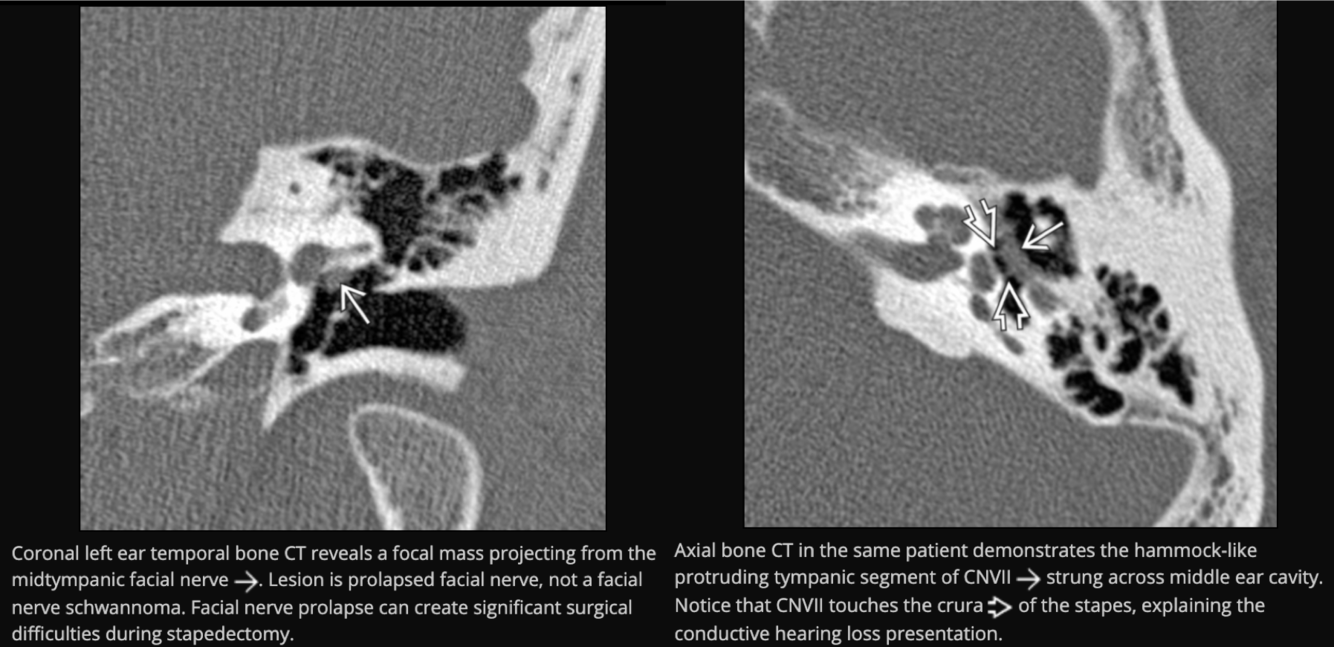

Prolapsing facial nerve (protruding intratemporal facial nerve)

Tubular soft tissue prolapsing into oval window niche from undersurface of LSC. Caused by dehiscence of bony covering of the facial nerve.

No enhancement! If enhances then it is a Schwannoma.

May project into oval indow.